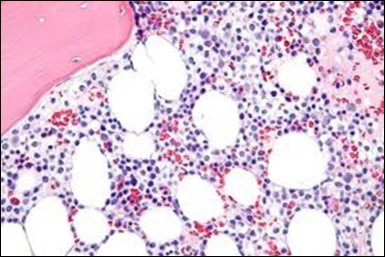

The classic hairy cell is medium sized with a magnitude of 10-14µm. The moderately abundant or variable cytoplasm may be transparent or mildly basophilic. The cellular surface with the characteristic serrated perimeter depicts innumerable fragile or stout extensions of cytoplasm ,particularly discernible on the phase contrast and electron microscopy. The cytoplasm may exhibit vacuoles with occasional azurophilic granules4. The nucleus may be elliptical or reniform, folded or indented with a coarse, reticulated or a finely dispersed chromatin and inconspicuous nucleoli along with infrequent mitosis. Bone marrow aspiration or bone marrow trephine biopsy may be inadequate for diagnosis in 30%-50% individuals4. The trephine sections of the bone marrow may depict a characteristic interstitial pattern of leukaemic infiltration. Generally the bone marrow is hyper-cellular, though it may be hypo-cellular in 10-15% individuals4. The leukaemia cell ingress may be diffuse or partial, although diffuse infiltration is frequent. The partial variety of leukaemic dissemination may be ineptly categorized with an indeterminate differentiation from the uninvolved marrow. The malignant insertions may initially emerge as miniature, undefined, cellular loci. The formalin fixed, paraffin embedded sections may elucidate a crystalline zone or a “halo” appearance of the cells with a circumscribed nucleus on account of the plentiful cytoplasm4. The cellular margins may be intertwined. Fixation of bone marrow smears with Zenker’s fixative may demonstrate a retracted cytoplasm of the hairy cells with a consequent disconnected structure. The bone marrow in the absence of a malignant process may be hypo-cellular or hyper-cellular. Reticulin stains may delineate an enhanced accrual of broad, dense reticulum fibres surrounding the aggregates of leukaemia cells with the fibrous circumlocution of individual malignant cell and fibrotic extensions into the abutting, uninvolved bone marrow4.

The leukaemia cells may enunciate a characteristic immune phenotype, crucial for a confirmatory diagnosis. The peripheral blood mononuclear B cell population may display a kappa or lambda light chain restriction. The phenotype of classic hairy cell leukaemia may be delineated by concurrent, immune reactive CD19+ CD20+,CD 11c+, CD25+, CD103+ and CD123+. An intensely immune reactive CD200+ and a non reactive CD27- antigen may be present2, 4. Evaluation of a trephine bone marrow biopsy and bone marrow aspirate may define the degree of tumour infiltration. A dry tap on account of prominent bone marrow fibrosis may be elucidated at preliminary diagnosis. A decline in the normal haematopoiesis may account for a hypo-cellular marrow in 10% instances. Gradation of cellular infiltrating of the leukaemia within the bone marrow may be appropriately investigated with immune –histochemical stains2, 4. Immune staining for CD20+, annexin 1 and VE1 (a BRAF V600E stain] may validate the diagnosis and precisely analyse the extent of malignant bone marrow infiltration[8]. Determination of BRAF V600E mutation may be critical in therapeutically non responsive individuals with applicable standard therapy or in instances of multitudinous reoccurrences[9]. Deploying inhibitors of BRAF V600E gene may be efficacious in patients impervious to approved therapy. The mutation necessitates a comprehensive scrutiny of the implicated individuals with a sensitive molecular assay which may discern up to < 10% of the hairy leukaemia cells appearing in the peripheral blood smears or bone marrow aspirates diluted with peripheral blood or aspirates elucidating a dry tap[2,4]. Allele specific polymerase chain reaction (PCR) or a next generation sequencing may be optimally employed to circumvent false negative outcomes. If the leukaemia cells are sparse or if particularly sensitive & efficacious molecular techniques are not accessible, the application of appropriate immune histochemical stains to the bone marrow biopsy such as a BRAF V600E mutation stain (VE1) may detect the hairy cells and conclusively diagnose the condition[2,4,10]. Figure 1, Figure 2, Figure 3, Figure 4, Figure 5, Figure 6, Figure 7, Figure 8, Figure 9, Figure 10, Figure 11, Figure 12, Figure 13, Figure 14.

Figure 1.HCL: hairy cells infiltrating designated spaces(17).

Figure 2.HCL: hairy cells with projecting cytoplasm abutting bony trabaculae(18).

Figure 3.HCL: hairy cells dispersed within the native architecture(19).

Figure 4.HCL: hairy cells with widely spaced nuclei(20).

Figure 5.HCL: hairy cells with infiltration in the spleen(21).

Figure 6.HCL: disseminated hairy cells with a clear cytoplasm(22).

Figure 7.HCL: blebs on the cellular surface with fine nuclear chromatin(23).

Figure 8.HCL: widely disseminated hairy cells within the bone marrow trabaculae(24).

Figure 9.HCL: hairy cells within a bone marrow trephine biopsy(25).